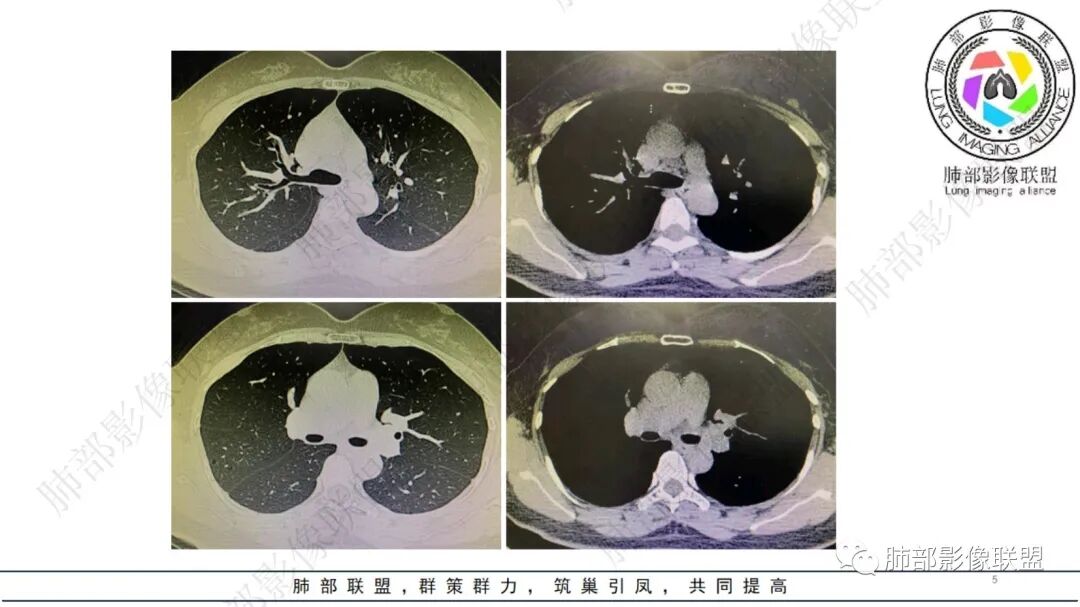

看纵隔窗:实性成分密度不高,囊张力高,内有间隔,偏胸膜侧,实性部分内部支气管聚集。

实性区域边缘平直、凹陷

首先囊的位置?为啥没考虑是空洞?空洞张力偏低一些,一般在中央一些,所以不太支持,纵隔侧几乎无壁,不太支持空洞。

囊实性?这部位,第一印象要警惕--隔离症

隔离症——需要增强确定,看起来附近似有体动脉正常,没增强底气不足。

真菌?不太符合,因为囊腔。如果不考虑隔离症?就要警惕腺癌系列,总体看来不是很支持。

1、右肺上叶混合密度磨玻璃结节特征性较强,尤其是后段病灶,边界清楚,应高度警惕微浸润腺癌,这个不用纠结,我们可以等,定期复查行之有效。

左肺下叶背段脊柱旁病灶相当不规则,形态既不符合空洞,也未能围成一完整的囊圈影,未见典型的分叶、毛刺及清楚的磨玻璃晕,前方出入支气管轻度扩张,纵隔窗病灶密度偏高不均,临近胸壁未见侵入。双肺门及纵隔未见增大淋巴结。

客观评价,该病灶缺乏恶性肿瘤影像学特征,尽管我们不能排除恶性。

2、临床实践中,左下叶背段类似阴影并不少见,支气管肺组织猬集纵隔旁,常为含气不良,或伴慢性炎症,长期存在。

结合本病例:年轻女性患者,体检发现病灶。影像学表现为左下肺类囊腔样结节,整体边界清楚,实性区域边缘平直、凹陷,缺乏典型分叶毛刺、胸膜改变等,病灶也未显示清楚的磨玻璃勾边,病灶不大而肺门纵隔未见肿大淋巴结,综合考虑慢性炎性肉芽肿可能性较大。必要时可结合病理检查。

肺隔离症也偏内侧,常表现为混杂密度,含液囊性病灶为主。须查实体循环供血证据。